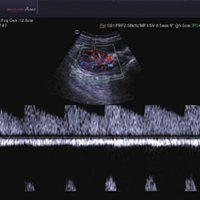

• 2D-Modus

• M-Modus

• Farb-Doppler

• Pulsed Wave (PW)-Spektral-Doppler

• Power-Doppler (PD)

• Directional Power Doppler (DPD)

• Color Opt Flow™ bietet kraftvollere Farben und verbessert die Bildqualität.